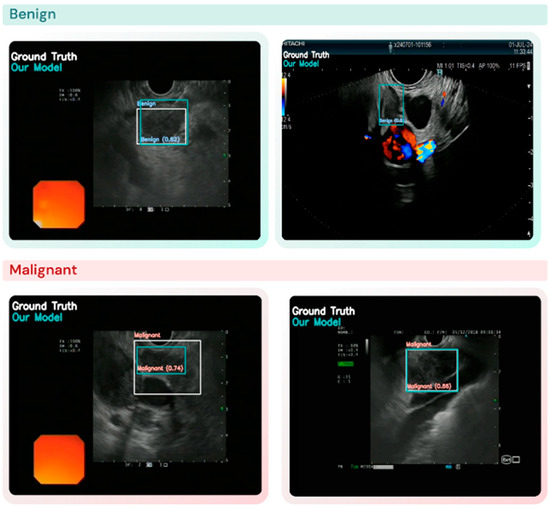

Finding the True Responders: Stratifying dMMR/MSI-H Tumors for ICI Response

Nari Kim, Seongwon Na, Jisung Jang, Mihyun Kim, Jun Hee Pyo and Kyung Won Kim

Background/Objectives: Immune checkpoint inhibitors (ICIs) show durable efficacy in tumors with deficient mismatch repair (dMMR) or high microsatellite instability (MSI-H), yet clinical responses remain heterogeneous. This study aimed to define immune subgroups within dMMR/MSI-H tumors and develop a reproducible transcriptomic signature predictive of ICI response. Methods: Four MSI-H-enriched cancer types (UCEC, COAD, READ, STAD) from The Cancer Genome Atlas were analyzed. Tumors were stratified by immune cell infiltration (MCP-counter immune composite score) and T-cell-inflamed gene expression profiles (GEP score). Integrating these two axes defined four immune subgroups. Differential expression, random forest feature selection, and pathway enrichment were performed to identify immune programs. A 20-gene immune signature representing the most immune-active subgroup was developed and validated across TCGA, GEO (GSE39582), and IMvigor210 cohorts. Results: Among the four subgroups, the most immune-active group showed strong activation of interferon signaling, antigen presentation, and T-cell-mediated pathways. The 20-gene signature—including CD74, STAT1, TAP1, and HLA-class genes—achieved high reproducibility (mean AUC = 0.95 ± 0.02; accuracy ≈ 89%). In the IMvigor210 cohort, this signature identified tumors with higher PD-L1 blockade response (55.6% vs. 32.8%, p = 0.034) and improved survival trends in the TMB-high subset. Conclusions: The proposed 20-gene signature quantitatively captures immune heterogeneity in dMMR/MSI-H tumors and serves as a practical, interpretable biomarker to identify true ICI responders and guide precision immunotherapy.